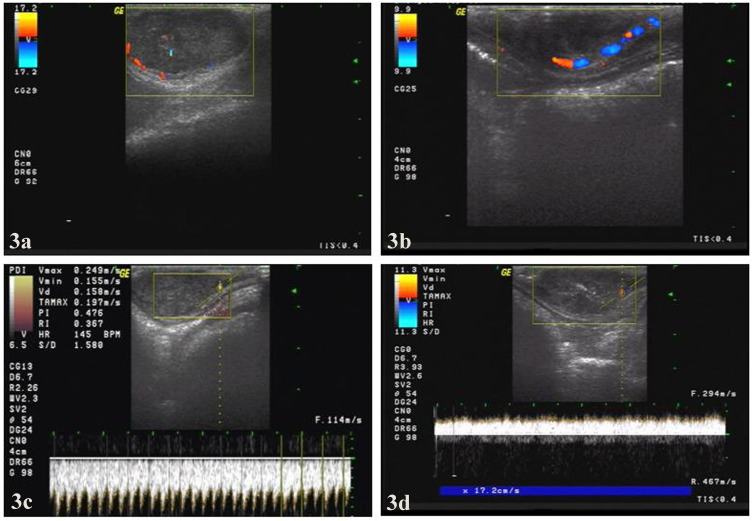

背景:本研究旨在探讨高频超声(US)对兔VX2乳腺肿瘤组织形态和血流动力学的影响,以及超声引导下经皮微波凝固(PMC)治疗兔VX2乳腺肿瘤的有效性和安全性。方法:20只VX2荷瘤兔,采用彩色多普勒超声检查肿瘤的生长特征,包括回声、大小、血供及血流动力学参数,每周1次,连续6周。随后,在随机分配的10只VX2荷瘤兔(另外10只作为对照)中进行us引导PMC。获得消融后的超声图像并进行分析。3只双VX2肿瘤兔在消融第0、1、4周作病理观察。通过肿瘤生长情况、体格检查、生存时间、肿瘤生存率、转移情况及组织病理学等指标评价治疗效果。结果:超声监测显示肿瘤生长速度为463.09%,第2 ~ 3周,在实时超声引导下行PMC。经微波消融后,部分肿瘤在第8周明显缩小或无法检测到。此外,美国没有检测到流量信号。治疗组和对照组2、3个月生存率分别为100%、70%和10%、0%,转移率分别为10%、30%和90%、100% (p结论:超声显像监测兔VX2乳腺癌的增殖和转移,超声引导下经皮微波消融治疗兔乳腺癌是一种安全、有效、微创的治疗选择,具有潜在的临床适用性。

Methods: Twenty VX2 tumor-bearing rabbits were assessed using color Doppler ultrasound for tumor growth characteristics including echo, size, blood supply and hemodynamic parameters once a week for six weeks. Subsequently, US-guided PMC was performed in randomly assigned ten VX2 tumor-bearing rabbits (the other ten as controls). US images after ablation were obtained and analyzed. Three rabbits with double VX2 tumors were used as pathological observation at weeks 0, 1, and 4 of ablation. The therapeutic efficacy was evaluated by tumor growth, physical examinations, survival time, survival rate and metastasis of tumors and histopathology.

Results: Ultrasound monitoring indicated that the tumor growth rate was 463.09% at the 2nd to 3rd weeks, and PMC was performed during this period under real-time US guidance. After microwave ablation, some tumors were greatly reduced or undetectable at week 8. Moreover, no flow signals were detected by US. The survival rates at 2 and 3 months in the treatment group and control group were 100%, 70% and 10%, 0%, respectively, while the metastatic rates were 10%, 30% and 90%, 100%, respectively (P<0.05).